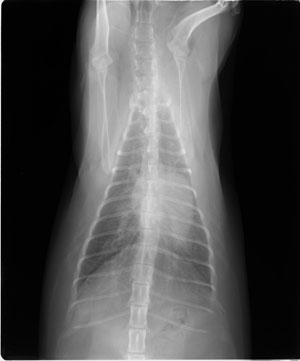

獣医師監修】猫の肥大型心筋症の診断と治療 著者:久保井春希 獣医師